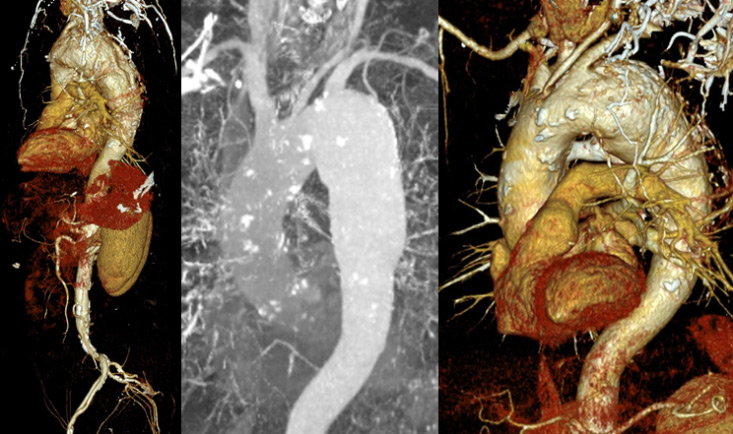

- Aortic arch aneurysm was treated endovascularly with a branched endograft one month later (May 2024)

- Branched TEVAR with custom-made Terumo Relay® double inner-branched endograft (46 x 32 x 270 mm) + distal extension (34 x 30 x 150 mm)

- Patency of endografts

- Aneurysm exclusion

- No endoleaks